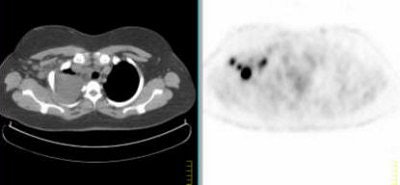

![]() |

Above, multiple axillary nodal metastases, SUV all > 2.3. Below, primary breast tumor with SUV 7.4. Images courtesy Dr. Alan Waxman.